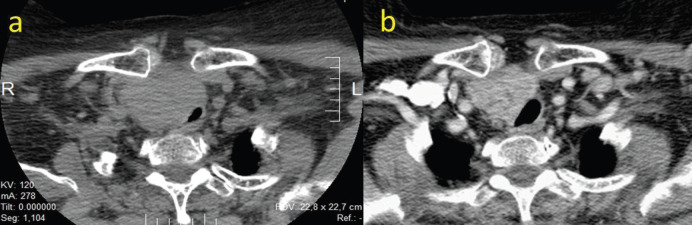

Case report: A 69-year-old female patient presented with a large mass in the right thyroid lobe measuring 10 × 8 cm. A computed tomography scan showed a mass with no cleavage plane between the tumour and both the laryngotracheal and esophageal right lateral wall. A core needle biopsy was performed and confirmed PDTC. The case was considered unresectable. After a trial of neoadjuvant lenvatinib was administered, a partial response of 50% was achieved and surgery could be performed with favourable surgical outcomes. The patient did not resume lenvatinib after surgery, as no evidence of structural disease was found. At publication, she remains free of structural disease with an incomplete biochemical response.